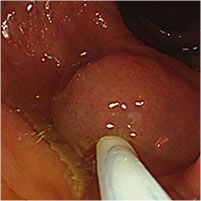

大腸ポリープ(NBI、狭帯光観察と大腸ポリープ切除)

大腸ポリープ切除

診断から治療まで一貫して対応ができるため、検査の際に万が一、ポリープを発見した際には即日の切除手術を行うことも可能です。

ポリープとは粘膜の表面に盛り上がってできるもので、病名ではなく形態を示します。ポリープには良性のものと悪性のものがあり、大腸の場合は良性と言っても悪性化することのない過形成性ポリープと、見つかった時は良性でも、そのまま切除せずに放置することで数年後にがんに変わる可能性のある大腸腺腫があります。大腸腺腫ががんに変わるリスクや時期を予測することはできません。大腸カメラ検査での早期検診、がん化する前の段階でポリープを取り除くことが大切です。